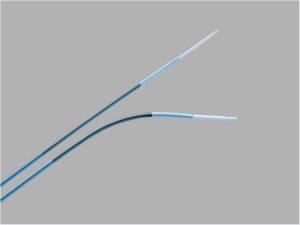

Endoprótese ramificada para aneurisma Toracoabdominal ZENITH® T-BRANCH®, indicada para o tratamento endovascular de pacientes de alto risco com aneurismas Toracoabdominais. Possui Sistema de entrega H&L-B One Shot hidrofílico e aramado de 22Fr.